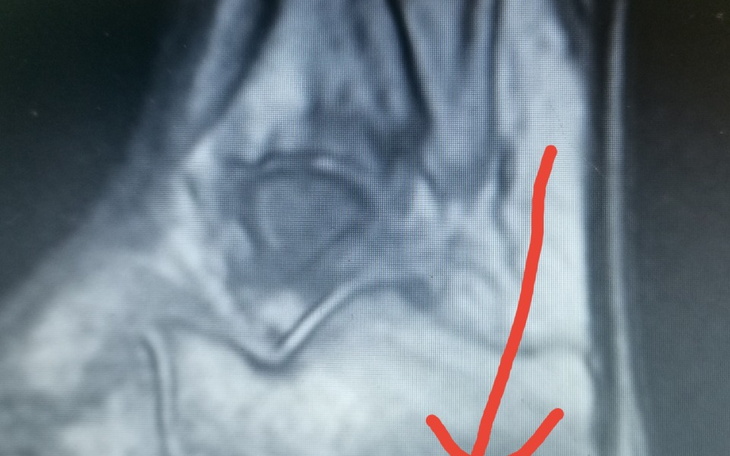

Od 5 lat mecze się z bólem stopy. Ganianie od lekarza do lekarz, brak diagnozy. Silny ból w stawie skokowym, opuchlizna. Okazalo się po ponad roku iż mam RZS, i przez to moja stopa tak długo goiła uraz. Niestety staw skokowy jest zniszczony, każdego dnia żyje z bólem. Do tego doszedł uraz złamania pięty, który się dość długo goi. Może dzięki wam uda mi się uzbierać na dobrą fizjoterapię by móc zaleczyć dobrze uraz i wrócić do pracy i normalnego funkcjonowania.